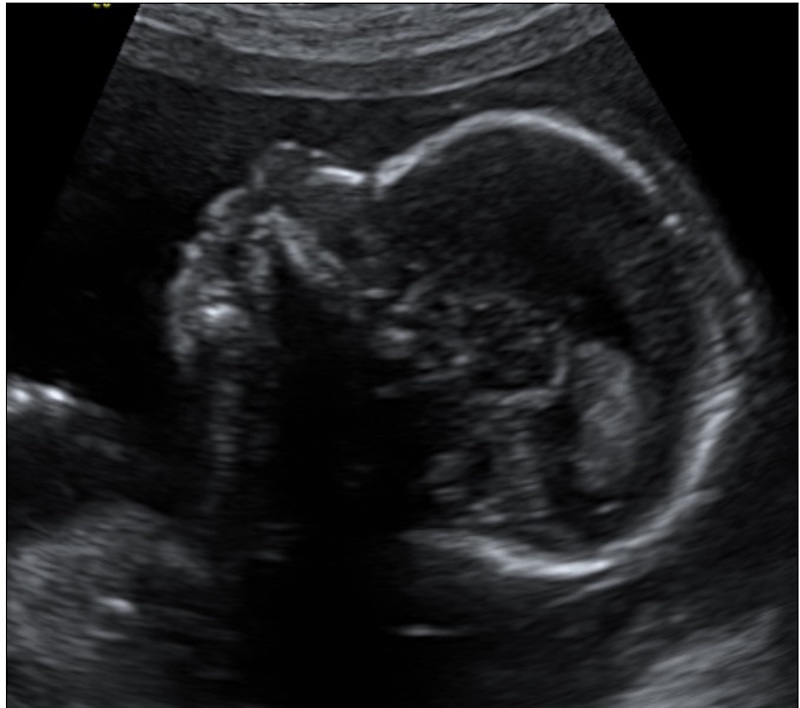

Crescimento fetal - dados brasileiros

A Organização Mundial de Saúde - OMS - redefiniu as referências de crescimento fetal e passou a requerer o uso de novo padrão internacional para avaliação do crescimento fetal por ultrassom.